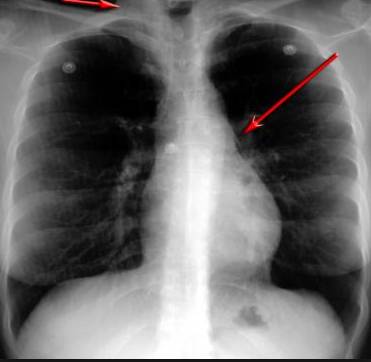

并且,因為呼吸系統(tǒng)結(jié)構(gòu)復(fù)雜,在體檢時醫(yī)生很難通過一種檢測手段,判定早期患者的病情。

把整個肺部看得清清楚楚!

使用這臺掃描儀,將直接把器官變成3D圖形!細(xì)微的毛細(xì)血管,幾毫米大的肺泡和支氣管,都將能看的一清二楚!

你的每一個氣泡,每一段支氣管,哪兒有病變都清清楚楚的將展示在醫(yī)生面前!

也就是說在一切都還沒開始惡化前,把這些有問題的器官組織都暴露的一清二楚:

沒有這項新技術(shù),醫(yī)生在做體檢的時候,很難通過一種測試斷定一個人是否有呼吸系統(tǒng)疾病。

可是現(xiàn)在他們不但能看到整個肺部的3維結(jié)構(gòu)圖。還能看到空氣進(jìn)入人體后的所有微小變動!